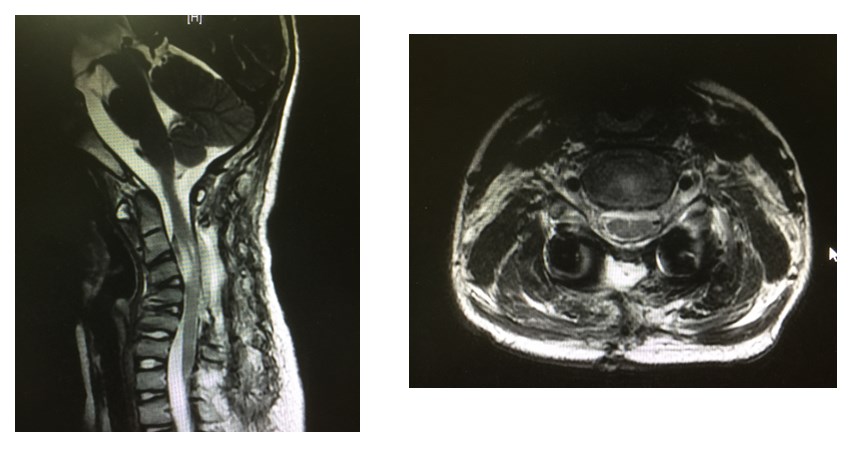

手术后5天复查,囊肿完全切除,颈椎曲度逐渐恢复